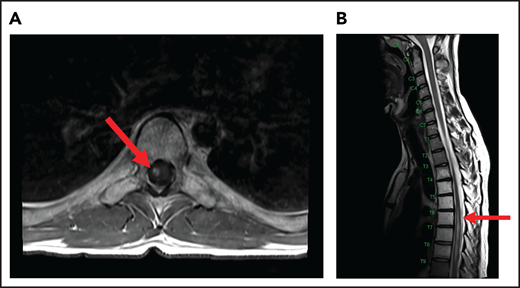

A 24-year-old man presented with stage IVB DLBCL and completed 6 cycles of R-CHOP, with FDG-PET after treatment showing resolution of all disease except in the mediastinum. After a biopsy of this residual FDG+-confirmed DLBCL, he received treatment with salvage chemotherapy with minimal response, followed by mediastinal involved field radiation therapy (IFRT) to a dose of 40 Gy plus a 6-Gy boost, after which he had a CR. Subsequently, he underwent autologous SCT followed by RIC allogeneic SCT. He remained in CR for 16 months, at which time he presented with 3 weeks of new right leg weakness, erectile dysfunction, and urinary hesitancy. The results of a brain MRI were unremarkable, but a spine MRI demonstrated spinal cord expansion and edema with multifocal enhancement within the prior radiation therapy portal from T5 to T9, demarcated by fatty marrow replacement between the T5 and T9 vertebral bodies (Figure 4). A diagnostic evaluation, including CSF analysis, was negative for malignancy, infection, autoimmune or inflammatory conditions, or demyelination. He was diagnosed with radiation-induced myelitis. He was treated with HD-MTX and had a minimal response. Treatment with bevacizumab led to complete resolution of the lesion, and after intensive physical therapy, he regained neurologic function.

MRI of the cervical and thoracic spine of a patient with radiation-induced myelopathy. (A) Axial T1-weighted image after gadolinium contrast shows enhancement within the spinal cord. (B) Sagittal T2 image shows a signal change throughout the patient’s prior radiation portal from T5 to T9, demarcated by fatty marrow replacement between the T5 and T9 vertebral bodies.